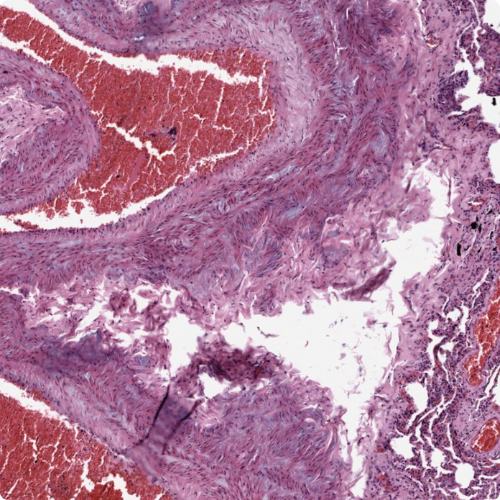

Clinical